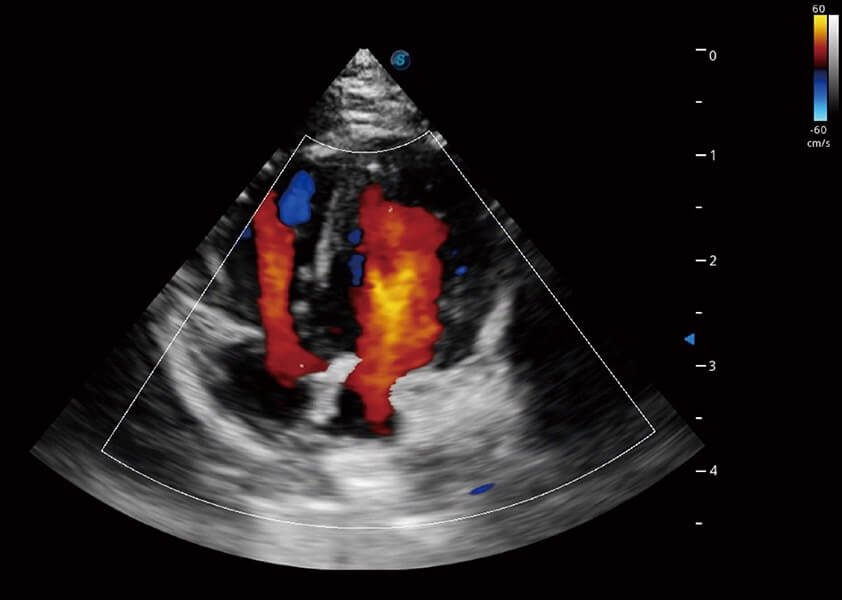

心脏解决方案

ProPet 60 配备了丰富的心脏探头群、先进的成像技术和专业的心脏测量工具,可帮助动物医生为不同体型和生理结构的动物提供心脏和心肌功能的全面评估。

(犬)四腔心血流

(犬)心脏组织多普勒